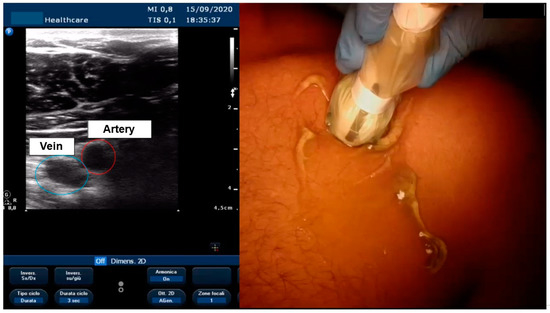

3.4. Ultrasound-Guided Vascular Access